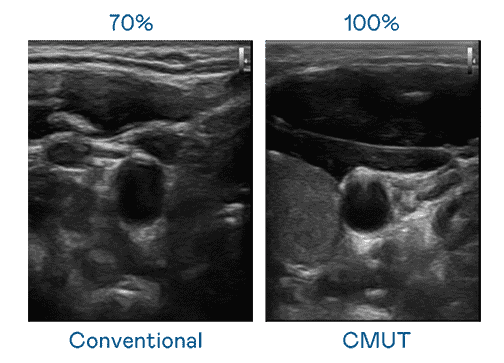

CMUT 技术是一种用电容式微机电元件来产生超音波讯号的技术。。与传统 PZT 压电式技术相比,,CMUT 频宽增加 30%,,更宽频的超音波讯号让影像解析度大幅提升,,是实现高影像品质医疗超音波扫描、、促进精准医疗发展的关键技术。。。

超音波影像的解析度高低,,首先取决于探头能发出的讯号频宽。。。。人生就是博 CMUT 可提供高清晰的超音波讯号,,提供高频宽、、高灵敏度、、、、影像纹理细节更高的超音波影像,,,协助医护人员缩短影像判读时间及利用精准的医疗影像进行诊断。。。